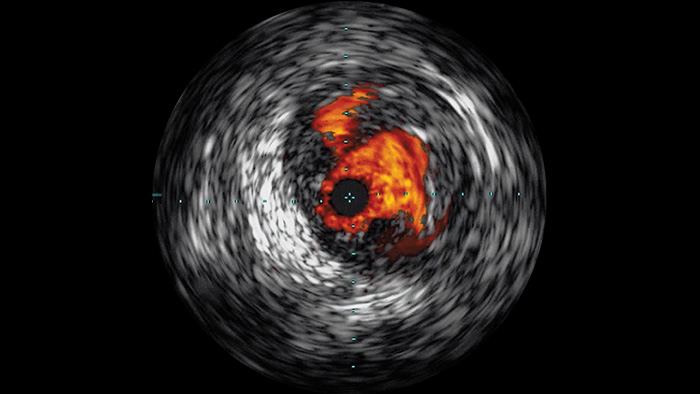

Intravascular ultrasound (IVUS) is a catheter-based imaging technology that allows physicians to visualize blood vessels from the inside out to aid assessment of presence and extent of disease. IVUS helps to decide, guide and confirm the right interventional treatment for each patient.

Visualizes high-definition images of vessels with outstanding vascular detail to support precise treatment strategies, navigation and follow-up.